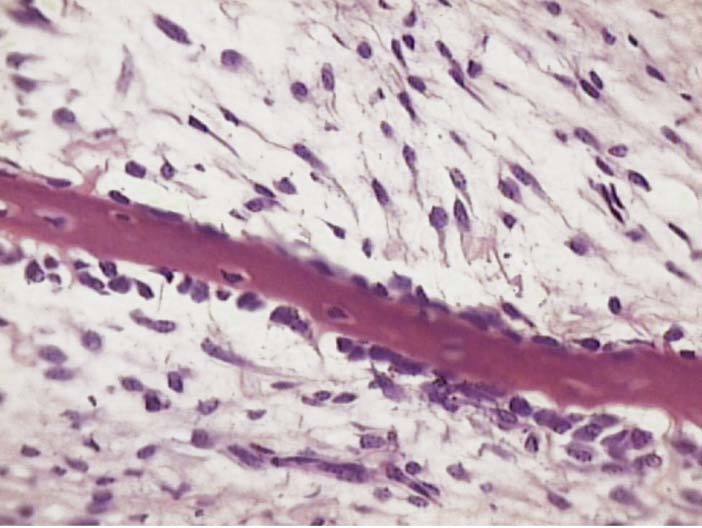

What type of ossification is occuring here?

Intramembranous Ossification